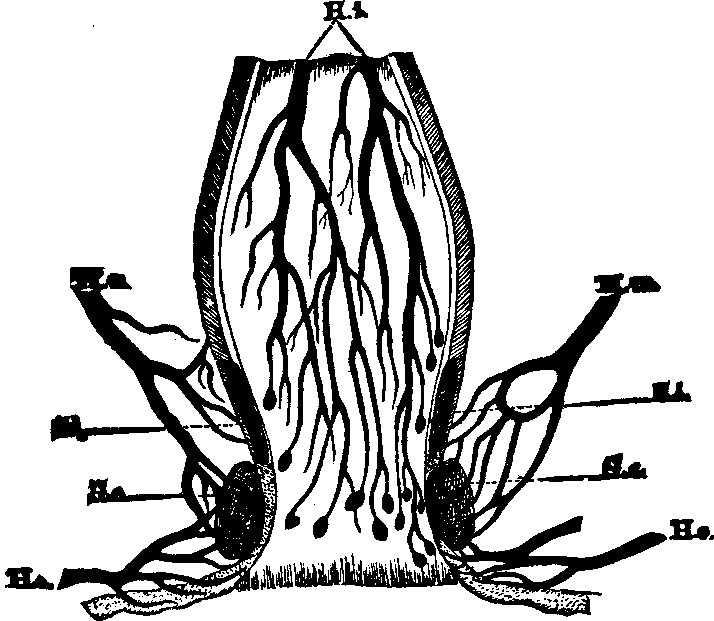

Fig. 14. Backbone, spinal

column, or vertebral column. All animals possessing such a row of bones are

called vertebrates. Above b are the cervical (neck)

vertebræ; b to c, dorsal (back) or chest

vertebræ; c to d, lumbar (loins) vertebræ;

d to e, sacrum; e to f, coccyx.